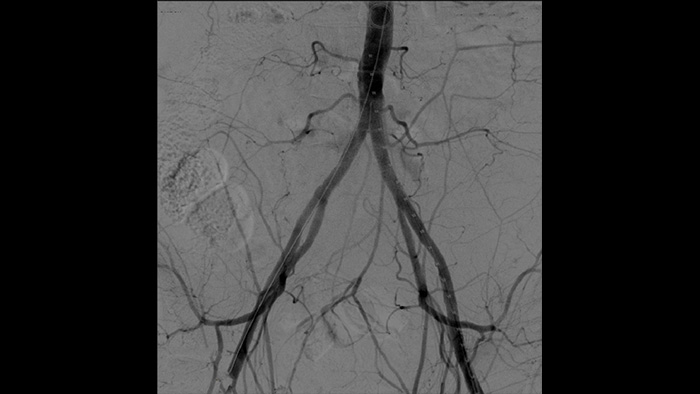

Uno de los principales especialistas en cirugía vascular mínimamente invasiva en España es el Dr. Ramón Vila, jefe del Departamento de angiología y cirugía vascular del Hospital Universitario Bellvitge, de Barcelona, España, que realiza 1000 cirugías vasculares al año. Con el arco en C móvil Philips Zenition, el Dr. Vila está obteniendo excelentes imágenes de alta calidad que le permiten realizar la mayoría de los procedimientos vasculares con dosis bajas.

Con Zenition, nuestra calidad de imagen de la ASD ha mejorado mucho. Ya no vemos una imagen granulada. Solo una imagen muy clara.

Tratamiento vascular

La angiografía por sustracción digital (ASD) se utiliza en procedimientos vasculares intervencionistas para ver con claridad los vasos sanguíneos mediante la eliminación de estructuras que pueden oscurecer la visibilidad de los vasos. La hoja de ruta de fluoroscopia superpone la imagen de contraste sustraída con anterioridad adquirida en la fluoroscopia en vivo, lo que le permite rastrear el dispositivo sin reinyectar el contraste.

Es más fácil ver un cable guía en comparación con nuestro antiguo sistema. Ahora se puede ver la punta y el ángulo del cable que está dando vueltas, incluso con cables de 0,014 pulgadas.

Esto se debe a que Zenition compensa lo que es metal y lo que se mueve.

Philips DoseWise Zenition es una combinación única de técnicas, programas y prácticas, integrada en nuestros sistemas de arco en C móvil Zenition que proporcionan una calidad de imagen clínicamente pertinente durante cada aplicación, al tiempo que gestionan la dosis de manera eficiente.